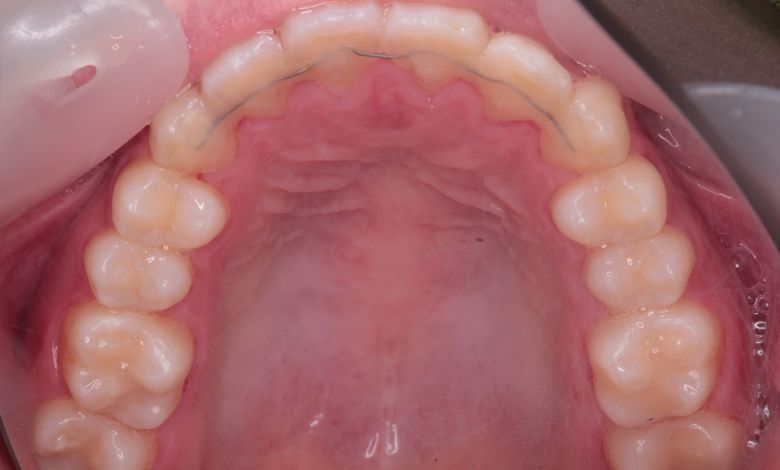

正常な咬合関係が確立され、前歯の自然なアーチと歯軸も整い、歯列全体が滑らかなカーブを描く美しい歯並びに

精密検査の結果、当院では抜歯を行わず、歯列弓の拡大によってスペースを確保し、非抜歯での矯正治療を選択しました。歯列の叢生(ガタガタ)は解消され、機能的かつ審美的に優れた咬合が得られました。

上顎歯列はV字型に近く、全体的にアーチが狭窄している状態

叢生が解消され、歯列全体にわたり滑らかで調和のとれた配列が得られています